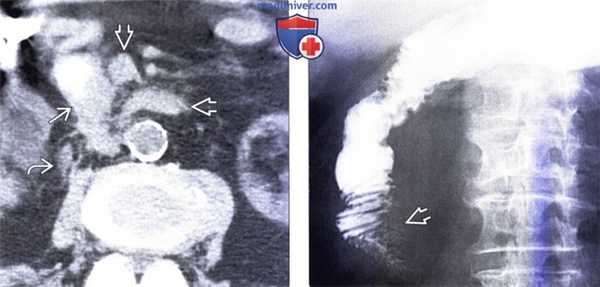

(Слева) На аксиальной КТ без контрастного усиления, выполненной мужчине 88 лет с жалобами на раннее насыщение и снижение веса тела, определяется растянутый желудок (не показан на представленном срезе). Определяется внезапное, эксцентрическое сужение просвета второй части двенадцатиперстной кишки. Опухоль распространяется, инфильтрируя расположенную поблизости жировую клетчатку, кроме того, имеет место регионарная лимфаденопатия.

(Справа) На рентгенограмме, полученной при рентгеноскопии верхних отделов ЖКТ у этого же пациента, определяется выраженная обструкция второй части двенадцатиперстной кишки, обусловленная скиррозным образованием, представляющим собою первичный рак.